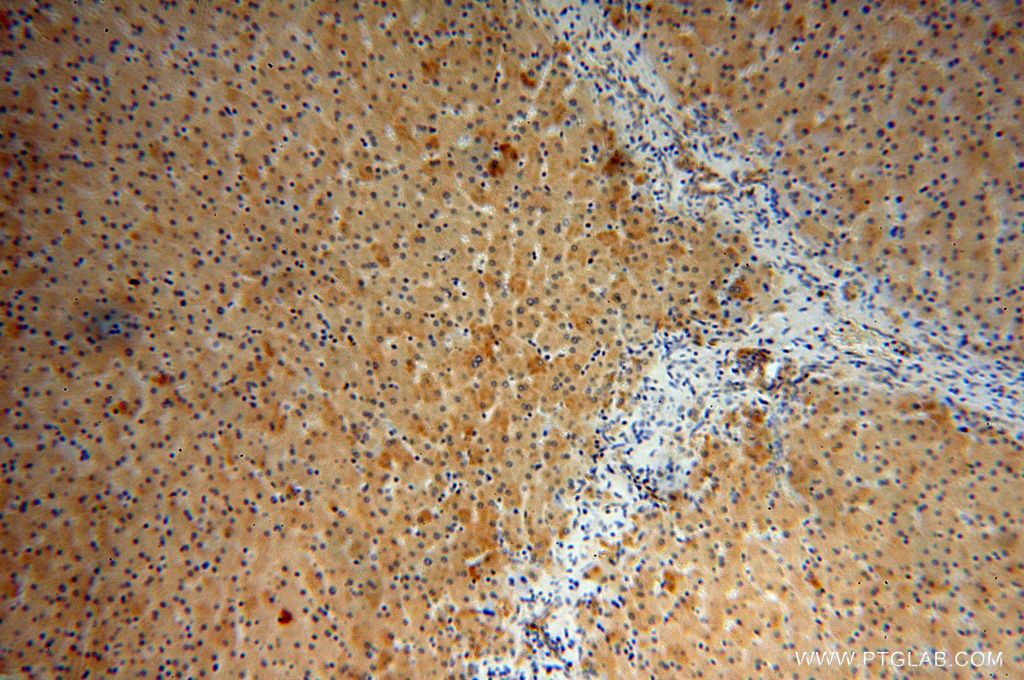

使用范围: WB,ELISA,IHC-P,IHC-F,IF